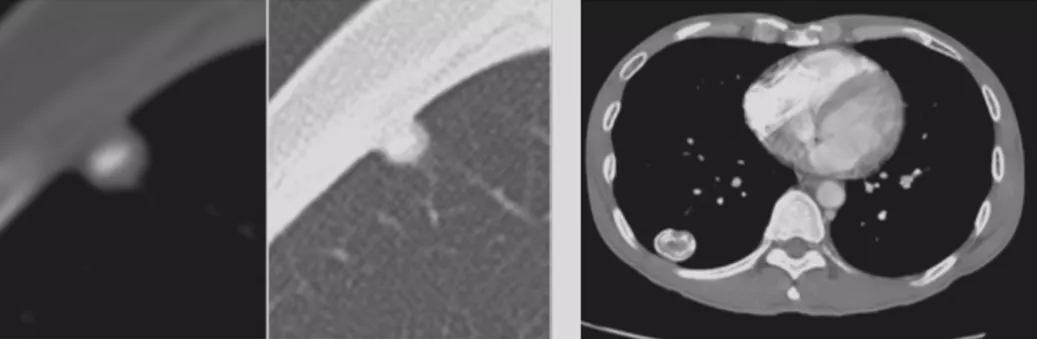

如上图所示,一般来说这么小的病灶我们可能忽略,但这个病人做了手术,不仅是恶性肿瘤,而且是微浸润腺癌。实际上我们在临床上要把这么多结节甄别出来,是十分具有挑战性的。病人一旦患有肺结节,也面临着很多问题,比如焦虑、心理压力等。所以我们既不能过度诊断,但也不能延误诊断。

小细胞肺癌

小细胞肺癌以中央型多见,但是也有少数为周围型病灶。多为单个实性结节或肿块,可见分叶、毛刺、血管集束征、胸膜牵拉征。实际上我们很难从影像学上判断出小细胞肺癌的病理类型,往往是活检或者手术以后才能证实。如下图示,这属于I期的小细胞肺癌,进行手术的效果非常好。所以对于周围型小细胞肺癌,如果在结节很小的时候判断出来就做了手术,疗效非常好。我们知道小细胞肺癌是肺癌中治疗效果最差的,恶性程度是最高的。如果早期手术,仍然能够起到很好的效果。